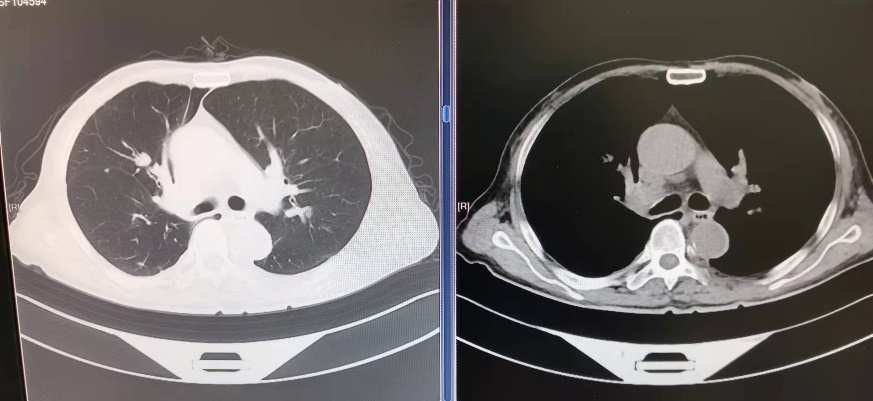

术前CT可见气管下端及右主支气管新生物阻塞管腔

术后CT见梗阻解除,气道通畅